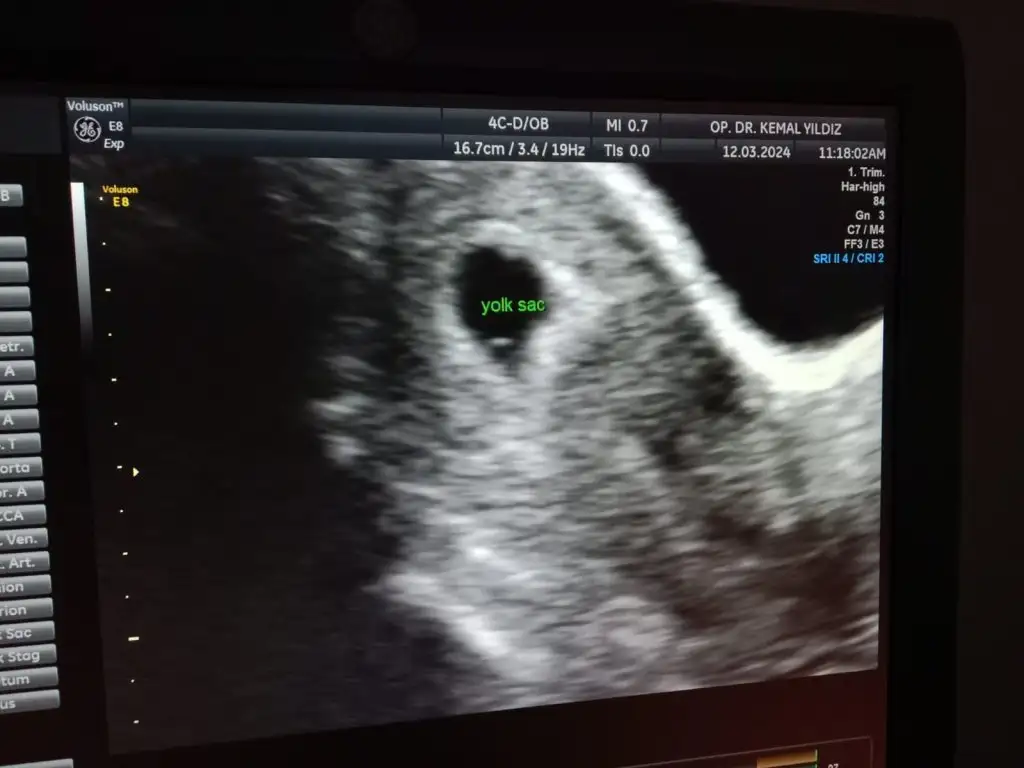

ay cok sevindim hayırlı olsun canım benimKızlar göbekten baktı çok şükür keseyi gördük yolk sac olusmus gayet düzenli gorunuyor kese dedi 16mm kese. Kalp atışı için 2 hafta sonra cagirdi

Çok şükür canım kalp için ne zamana gün verdiEki Görüntüle 3399778

Kalp atışı içinde haftaya gel dediEki Görüntüle 3399784